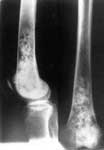

1.Опухоль нижней трети правого бедра.

2.Удаление опухоли с замещением дефекта в аппарате Илизарова.

3.Артродез коленного сустава.

4.Результат лечения.